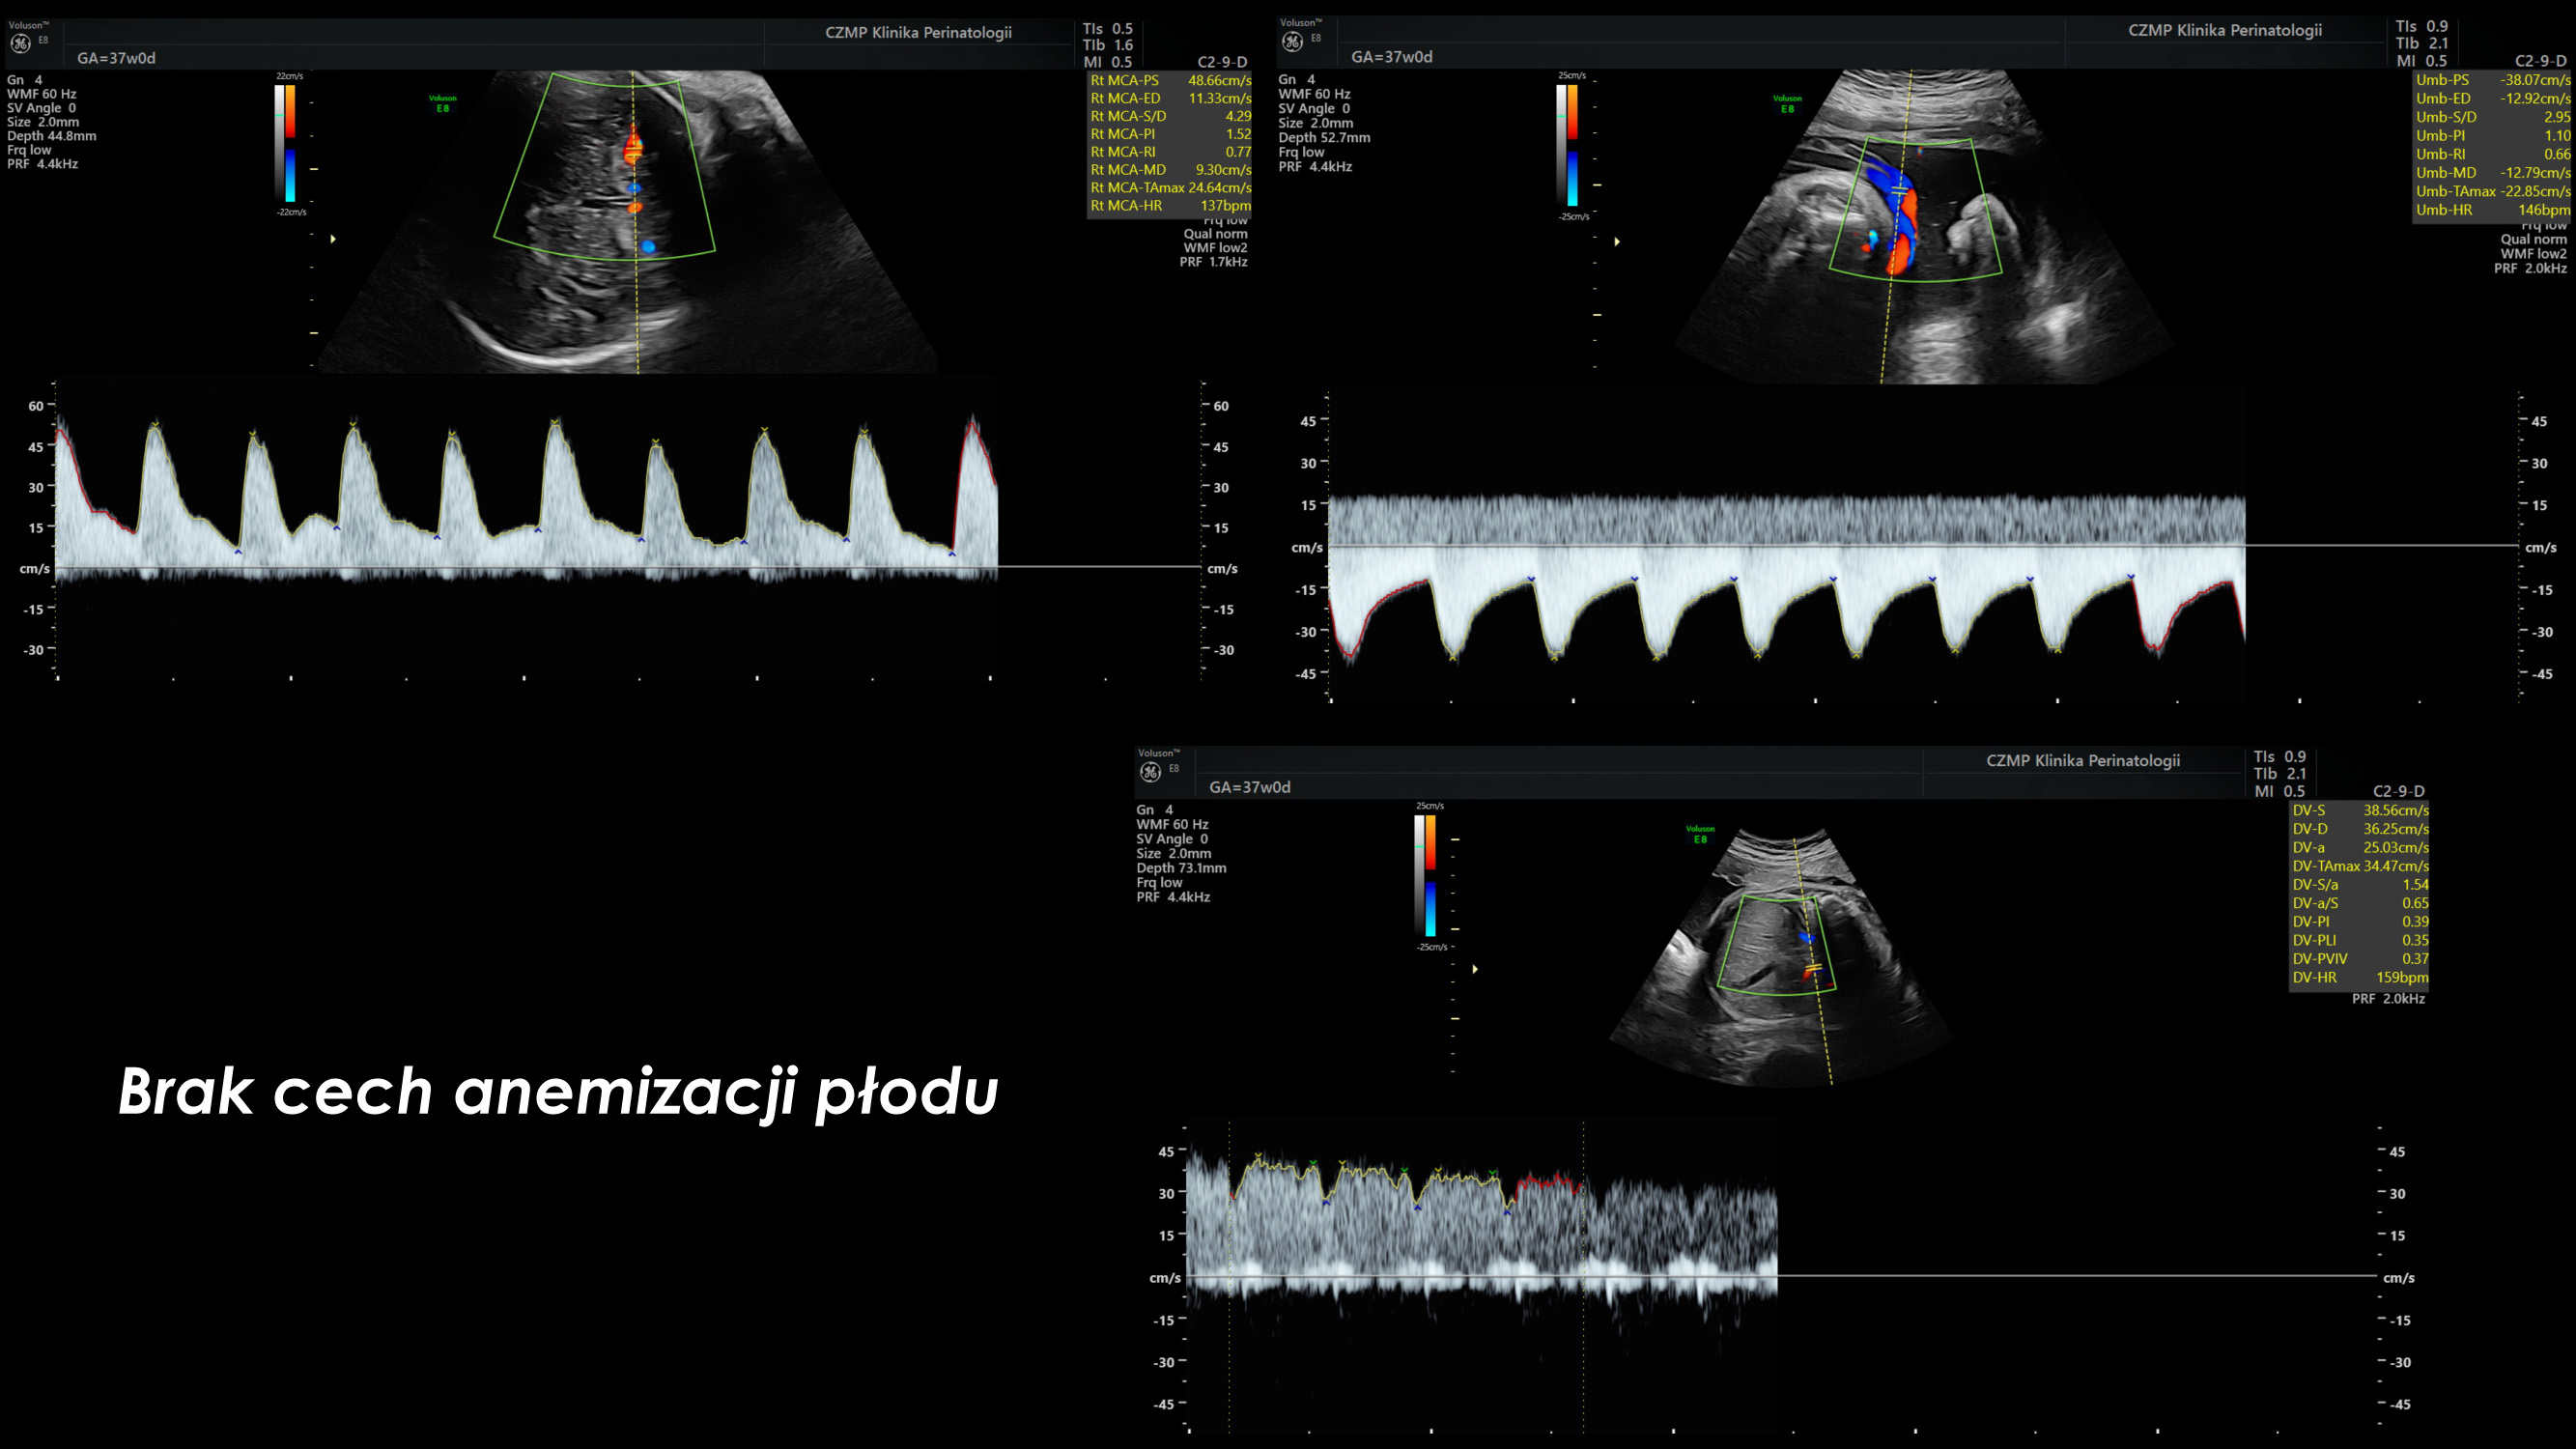

Nietypowy guz jamy brzusznej płodu